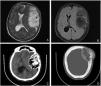

Skull vault hemangiomas are benign vascular tumours of the calvaria that are usually asymptomatic or present as firm, painless lumps. We present a case of a 59-year-old female with a giant intraosseous calvarial hemangioma that was admitted in our department with a palpable mass over the left frontoparietal region, personality changes and impaired emotional and cognitive functions. The patient was treated with a two-step approach involving endovascular and surgical treatment, and suffered two rare, but recognized complications, a contrecoup intracerebral haemorrhage and valproate-induced stupor and parkinsonism. At the 6-month follow-up, the patient had complete recovery with a good neurological outcome.